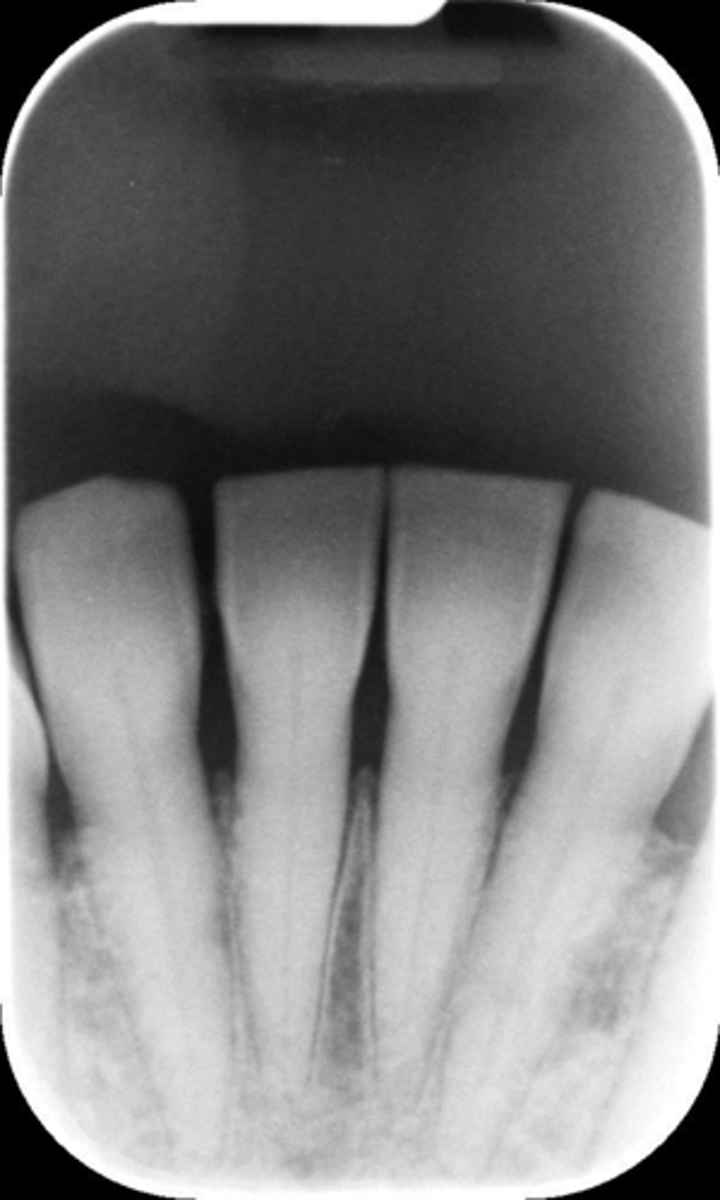

Cone cut, rotation

What is this error?

BID alignment problems cone-cuts

Appearance-A clear area appears on the plate

Cause-BID was not properly aligned with the periapical plate holder or, incorrect setting of the RINN instrument

Correction-Make certain the x-ray beam is centered over the plate

Rotation error

Can cause cone cut

Improper alignment of the BID*

Overlapping inter proximal contact ares*

This is a Rotation error, because just by rotating the BID toward the center of the plate, it can be avoided